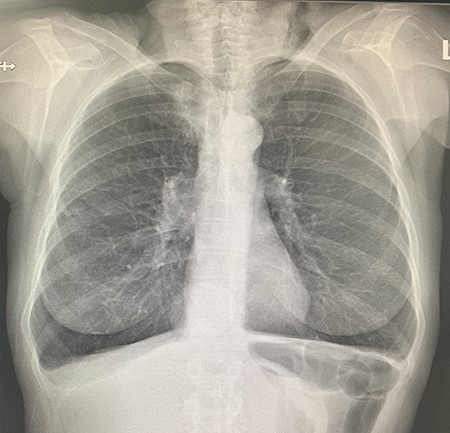

She presented to the operating theatre for excision with incidental dyspnoea and coryzal symptoms, and a pre-operative chest X-ray was arranged before any anaesthetic was administered, revealing a right upper lobe pulmonary mass partly obscured by the clavicle. She underwent excision of the cutaneous lesions, and respiratory physicians were consulted (Fig. 2). Urgent computed tomography (CT) chest was arranged, which revealed the diagnosis of lung malignancy, with a spiculating right apical mass measuring 48 × 30 × 29 mm, extending to the mediastinal pleura and in proximity to the oesophagus and posterolateral trachea with obliteration of the fat planes. There was also local hilar and paratracheal lymphadenopathy, measuring 30 × 29 × 20 mm in the right superior hilar region, 21 × 24 × 13 mm in the right inferolateral hilar region and a 36 × 14 mm pretracheal node (Figs 3 and 4). There were also background mild centrilobular emphysematous changes. There was no metastatic abdominal or pelvic disease.